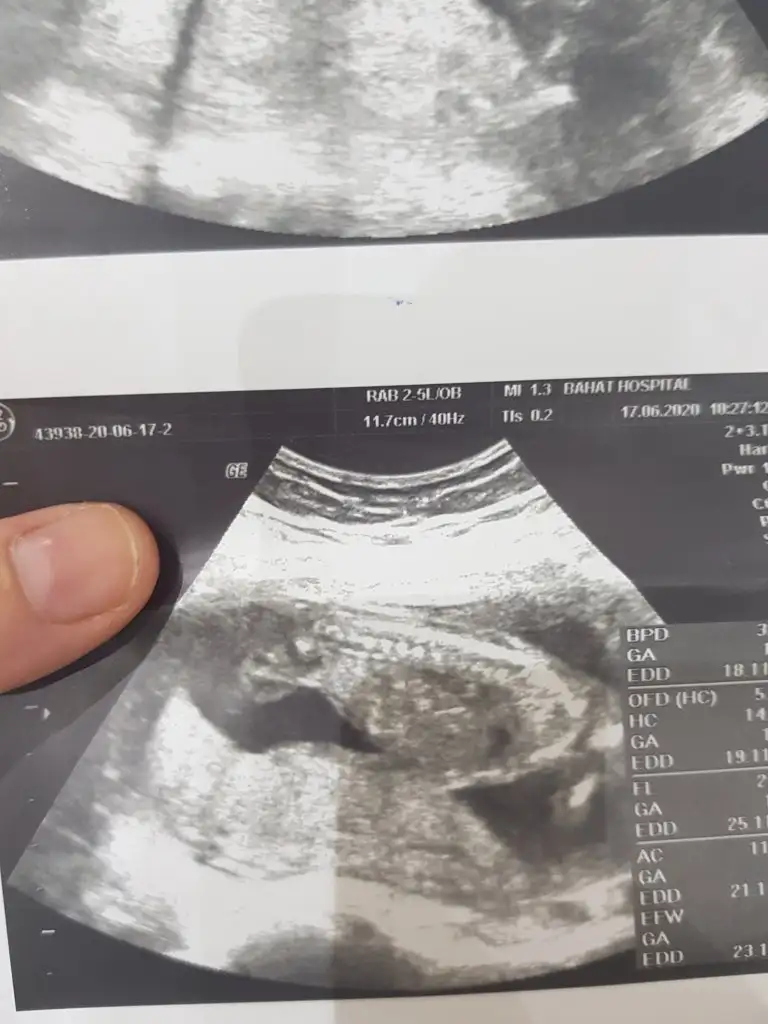

Sizin 12-13 hafta usg tekrar bakabilirmiyim 17 haftada artık nub olmaz ama orada sanki pipi gördüm gibi17 haftalik sız erkek demiştiniz doktor kız dedi ama çok kısa baktı ultrasonda yanılmış olabilir mi

17 haftalik sız erkek demiştiniz doktor kız dedi ama çok kısa baktı ultrasonda yanılmış olabilir mi